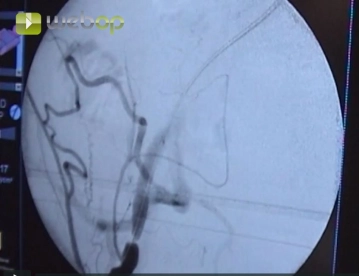

Punktion der Arteria femoralis communis in Richtung Arteria iliaca externa. Einführen einer 6F-Schleuse nach Seldinger. Hochführen des Führungsdrahtes unter Durchleuchtungskontrolle.